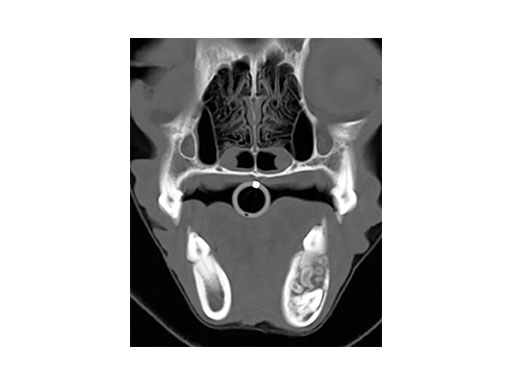

A 4-year-old castrated male cocker spaniel was admitted with a complex odontoma (confirmed by biopsy and histopathology) of the left mandible of 1.5 years duration. The CT image (Fig 3) shows the complex odontoma, and indicates an inhomogeneous mineral density within the mandible causing thinning/ disruption of the lateral cortex and tooth roots. The contiguous images demonstrated abnormal tissue spanning from PM3 to M1 of the left mandible.